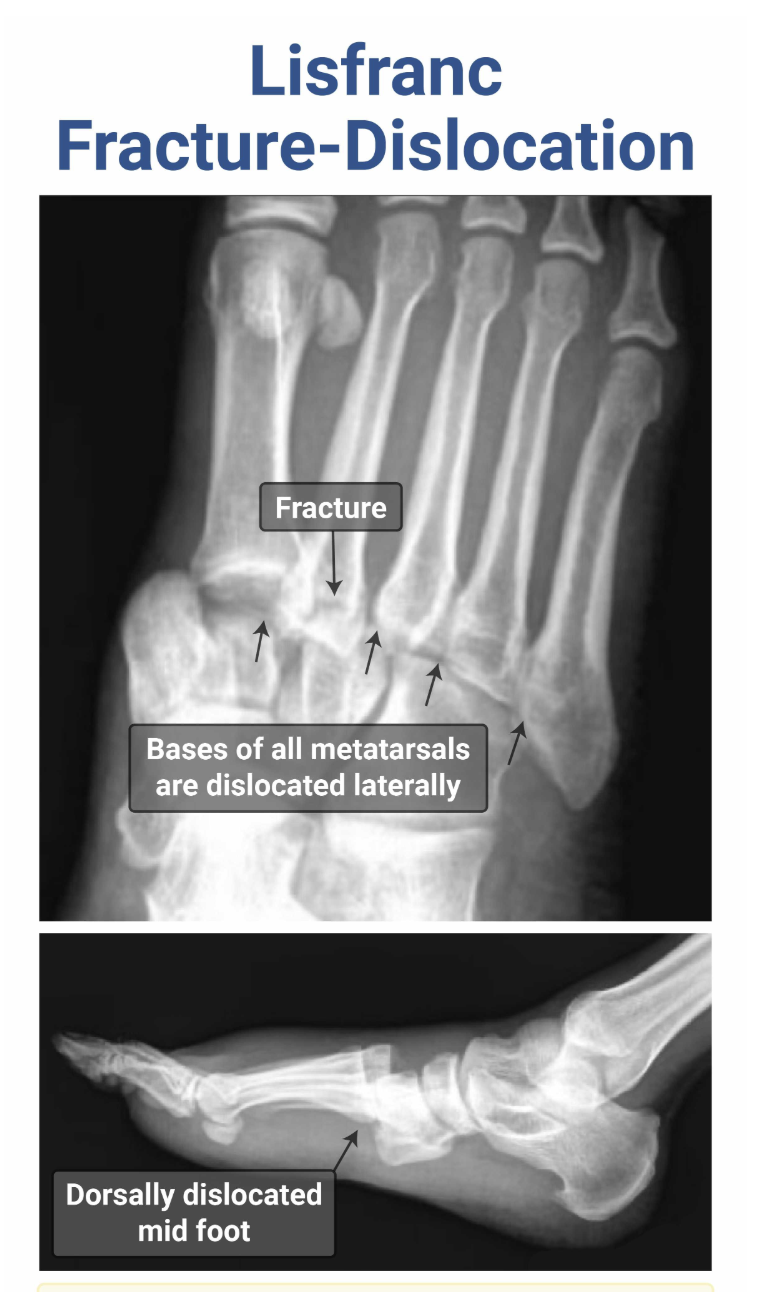

What is a Lisfranc Injury? Which joint is affected? Tx?

Lisfranc injury = fracture and dislocation of the tarsometatarsal joint, typically due to severe plantar flexion (sports, MVC, fall from heights), resulting in dorsal dislocation (pain is in dorsum of foot), may hear “clicking sound” on rotation of foot.

Tx: Immobilization, ortho ORIF